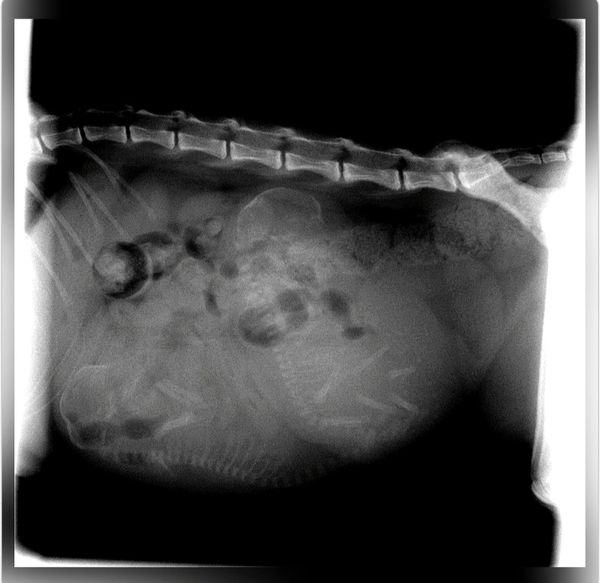

Honey is a very timid girl who was out for an evening walk with her Foster Carer. Suddenly without warning a large stray dog attacked Honey and her Foster Carer. Honey was hospitalised and underwent surgery. If you are able to help pay for Honeys Surgery we will be forever grateful.

Honeys hospital stay, surgery and treatment cost us $5482.88

HAPPY ENDING:

Honeys foster carer has officially adopted her.